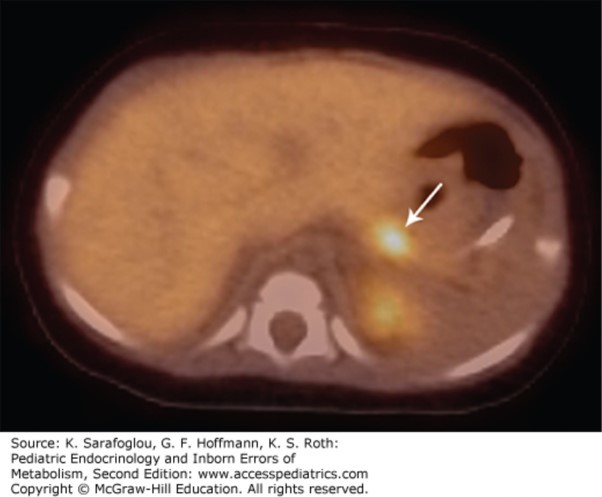

The correct answer is “A.” The fact that the infant is large for gestational age and has hypoketotic hypoglycemia in the absence of organomegaly is suggestive of hyperinsulinism. (See Figure 21–1.) Glycogen storage diseases generally present with organomegaly. Ketotic hypoglycemia is excluded by the text of the case study. (Were you reading carefully?) An organic aciduria is unlikely given the infant’s prominent hypoglycemia without prominent acidosis. Congenital disorders of glycosylation can cause hypoglycemia, although it is not prominently featured in CDG1a. Fatty acid oxidation disorders present after the neonatal period with hypoketotic hypoglycemia after fasting or during an illness.